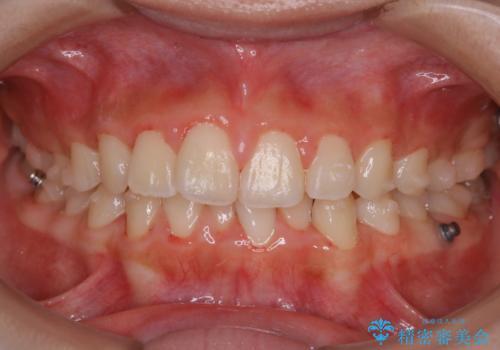

- インビザラインにて矯正治療中の方です。矯正治療の経過チェック時に歯磨き指導とクリーニングも希望とのことでした。